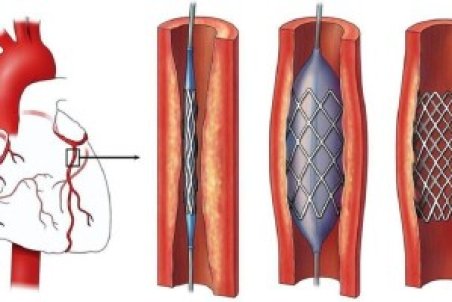

سکته قلبی چیست و چه علائمی دارد؟؛ انواع سکته و روش درمان

سکته قلبی رایجترین بیماری قلبی است.اطلاعاتی از سکته قلبی، علت، علائم سکته قلبی خاموش، تفاوت حمله قلبی و سکته قلبی، طول عمر بیماران را با روش درمان بخوانید.

آنچه از سکته قلبی نمی دانید

بیماری های قلبی عروقی با ۱۸.۶ میلیون مرگ در سال کماکان رتبه اول علل مرگ و میر دنیا را به خود اختصاص داده اند. البته این بیماریها در سطح کشور و استان کهگیلویه و بویراحمد نیز روند افزایشی داشته که این گروه از بیماریها علل متعددی از جمله مصرف دخانیات، دیابت،

علائم سکته قلبی؛ از خُروپف تا اختلال نعوظ

سکته قلبی عبارت است از صدمه به قسمتی از عضله قلب، که بهعلت انسداد در رگهای کرونری و از بین رفتن جریان خون در آن قسمت اتفاق میافتد. سکته قلبی ممکن است موجب مرگ فرد شود، به همین دلیل امروز در این مطلب قصد داریم به موضوع سکته قلبی بپردازیم.